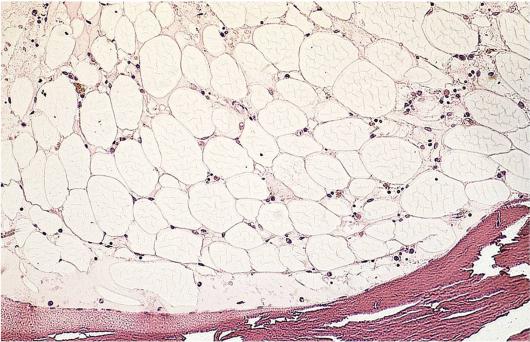

Апластическая анемия

Заболевание, чаще имеющее аутоиммунный механизм развития

Характеризуется уменьшением миелопоэза с замещением кроветворных клеток жиром

В анализе крови выявляется разной степени выраженности панцитопения

Анемия гипорегенераторная или арегенераторная (полное отсутствие ретикулоцитов)

Трепанобиоптат крыла подвздошной кости. В большинстве костномозговых полостей видно полное замещение кроветворной ткани жиром.